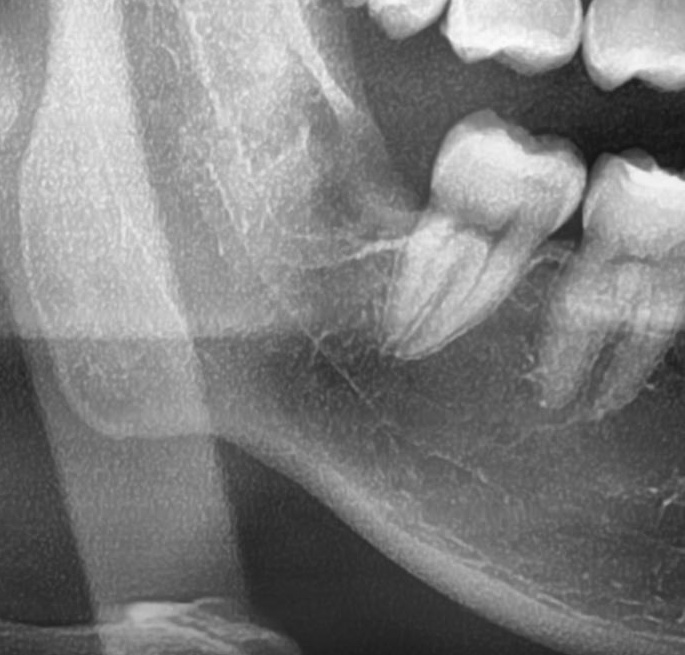

続いて2人目の患者様。

年末に右下の歯茎が腫れたとのこと。

確認してみると、右下の親知らずが歯茎の中でやや斜めに埋まっています。

抜歯開始。

抜歯終了。